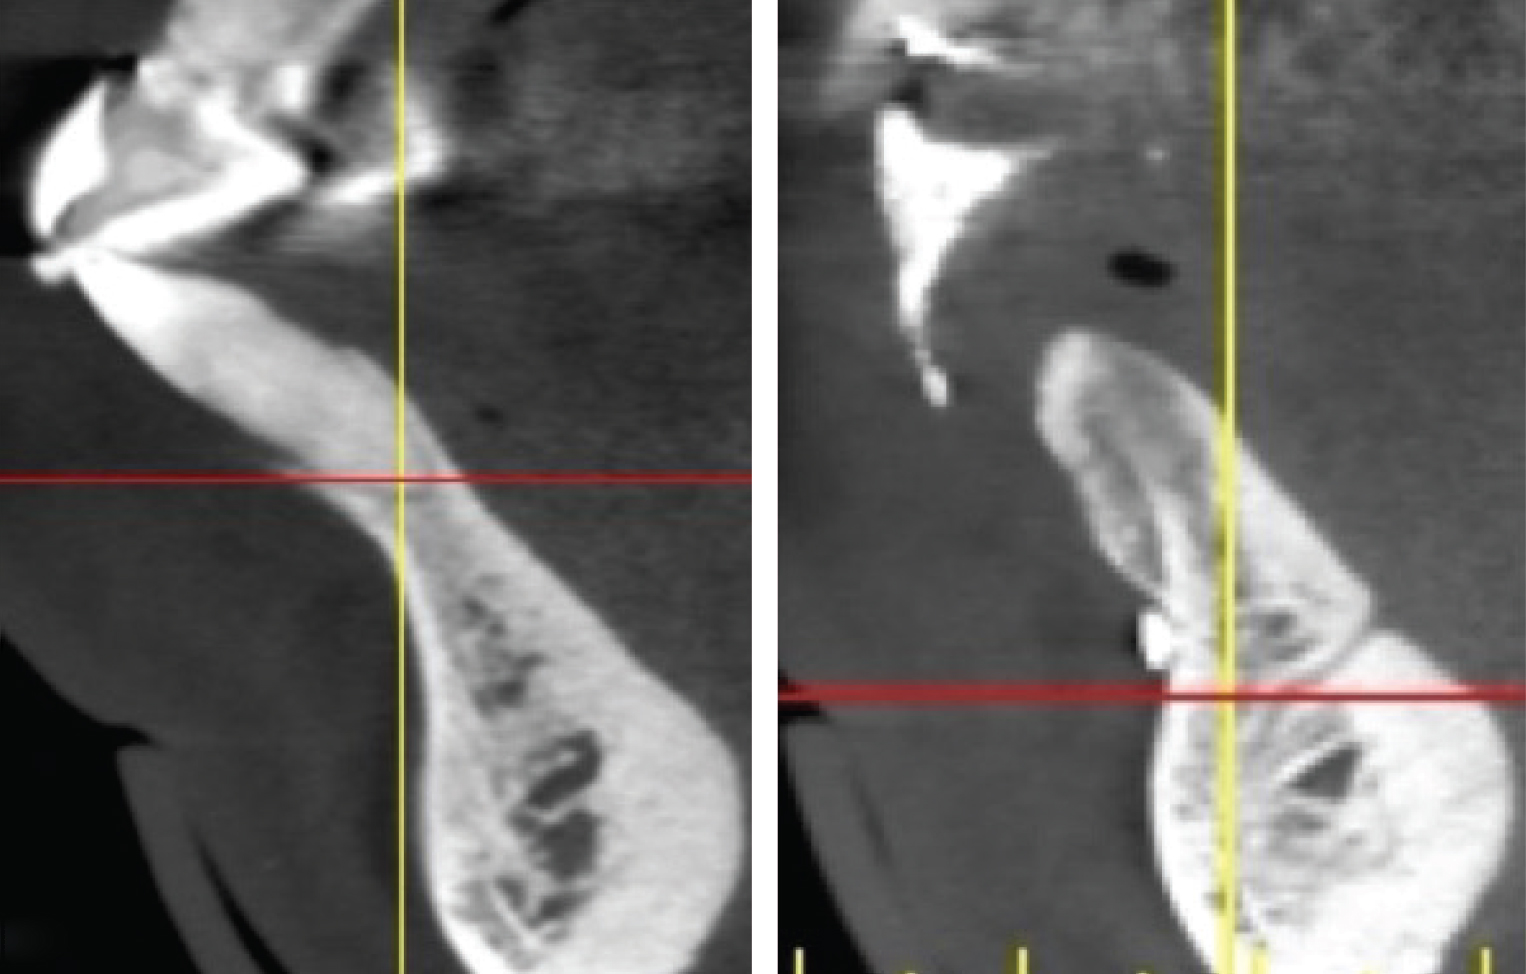

Figure 4

Sagittal cross-sections of CBCT images depicting Grade I (Left), Grade II (Center), and Grade III (Right) sockets. Note the level of the buc- cal plate relative to the cementoenamel junction that is elucidated by this cross-cut.